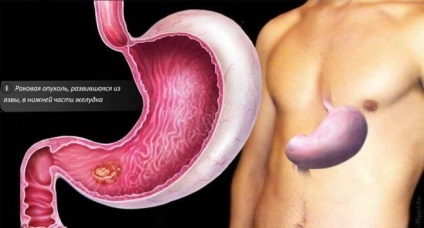

Gyomor rák ered malignus transzformáció hámsejtek. A 70-95% -ában ez a betegség által kiváltott a Helicobacter pylori baktérium, amely érintette a falat a gyomor. Ez a betegség hajlamosabbak évesek 50-70 év. A férfiak hajlamosabbak a betegség, rákos mintegy 15-20% -kal több, mint a nők. A kezdeti szakaszban a rák lehet kezelni, a cikk arról szól, módszerei a harc a betegség, valamint hány élnek gyomorrák.

- fekélyek;

- polipok a falak a gyomor;

- dysplasia a nyálkahártya;

- gyomorhurut.

Ennek első jele annak, hogy a jelenléte a betegség:

- gastritis (megnövekedett vagy csökkent savasság);

- fekélyek;

- polipok a falak a gyomor;

- metaplasia, dysplasia.